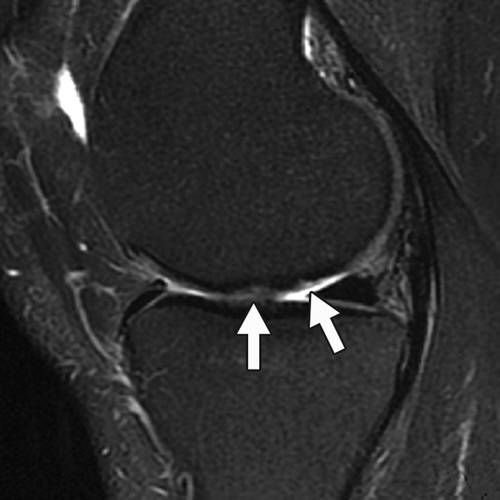

図12 Kellgren Lawrence による膝OA 重症度分類4 MRI を用いた臨床診断もさまざまな定量的な評価方法が報告されている813.先行研究 においては,関節軟骨変性の検出についての報告が多いが半月板を扱っているものもいく12骨挫傷および半月板損傷 膝痛の原因は様々ですが、膝関節内の半月板・軟骨・靱帯などの状態を調べるのに、MRI検査は非常に役立ちます。 この症例では脛骨の骨挫傷(→)と内側半月板後角損傷(*→)を認めます。 MRIトップ | 1乳腺疾患 | 2脳2 膝の固定方法 膝関節mriで最も重要な関節内構成要素のひとつに前十字靱帯(acl)がある。 mri機器に付属する膝用コイルのほとんどは円筒形であるが(図1),通常,円筒 形コイルに膝をセットし固定すると,膝は伸展位になる傾向がある。この場合,

半月板损伤的mri分级及检查 骨科基础 3u文域

半月板损伤mri是如何诊断的